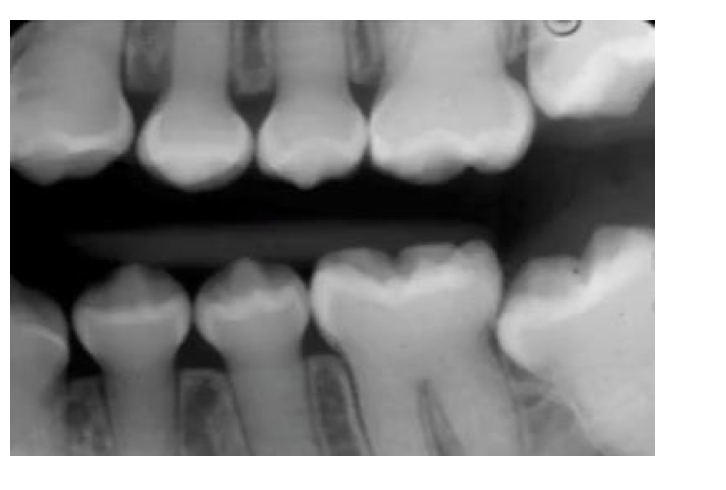

Ectodermal Dysplasia

X-Linked Recessive

Common Signs:

* Missing Teeth

* Multiple sharp pointed teeth

* Hypoplastic hair or nails

How well did you know this?